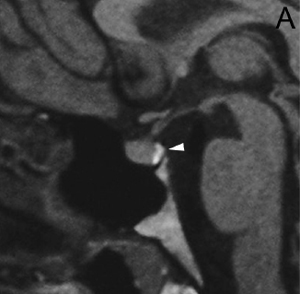

En los tumores grandes (macroadenomas) la TAC puede entregar información diagnóstica adecuada, pero no supera la definición que se logra con equipos de RM superconductores (Figuras 2 A y 2B).

Figura 2A y B. Cortes sagitales de RM y TAC. Adenoma pituitario con invasión del esfenoides y del clivus (puntas de flecha). Es posible demostrar las estructuras óseas en RM con similar precisión que la TAC.